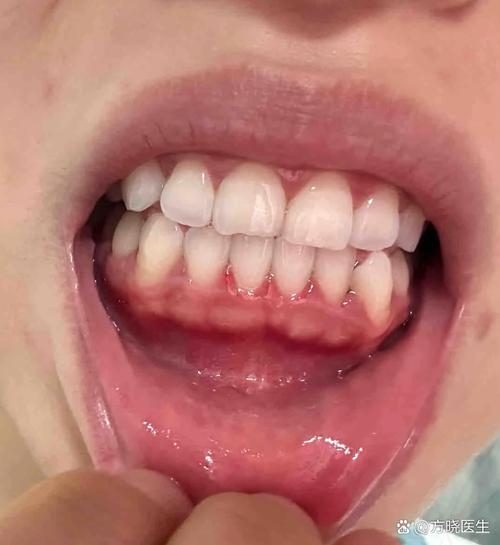

牙槽植骨术后“发白”现象的表现

牙槽植骨术后,植骨区域及周围黏膜可能出现发白,这一表现因人而异,具体特征如下:

- 发生时间:多出现在术后1-3天,部分患者可持续至术后1-2周,甚至更长时间(取决于植骨材料和个体愈合能力)。

- 部位与范围:发白区域通常位于植骨区表面黏膜,可能覆盖整个植骨区域,或延伸至周围牙龈,边界可清晰或模糊。

- 伴随症状:正常发白多无自觉症状,或伴有轻微肿胀、疼痛(术后正常反应);异常发白可能伴随明显红肿、疼痛加剧、异味、脓性分泌物,甚至黏膜糜烂、溃疡。

- 黏膜状态:正常发白时黏膜表面光滑,有弹性,与周围组织界限清晰;异常发白时黏膜可能失去光泽、变薄,触之易出血,或出现破溃、坏死。